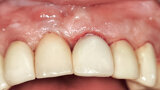

Fig. 12a: A post fracture presenting in the left central incisor, requiring extraction.

Fig. 12b: The occlusal view illustrated the cervical tissue volume and contours.